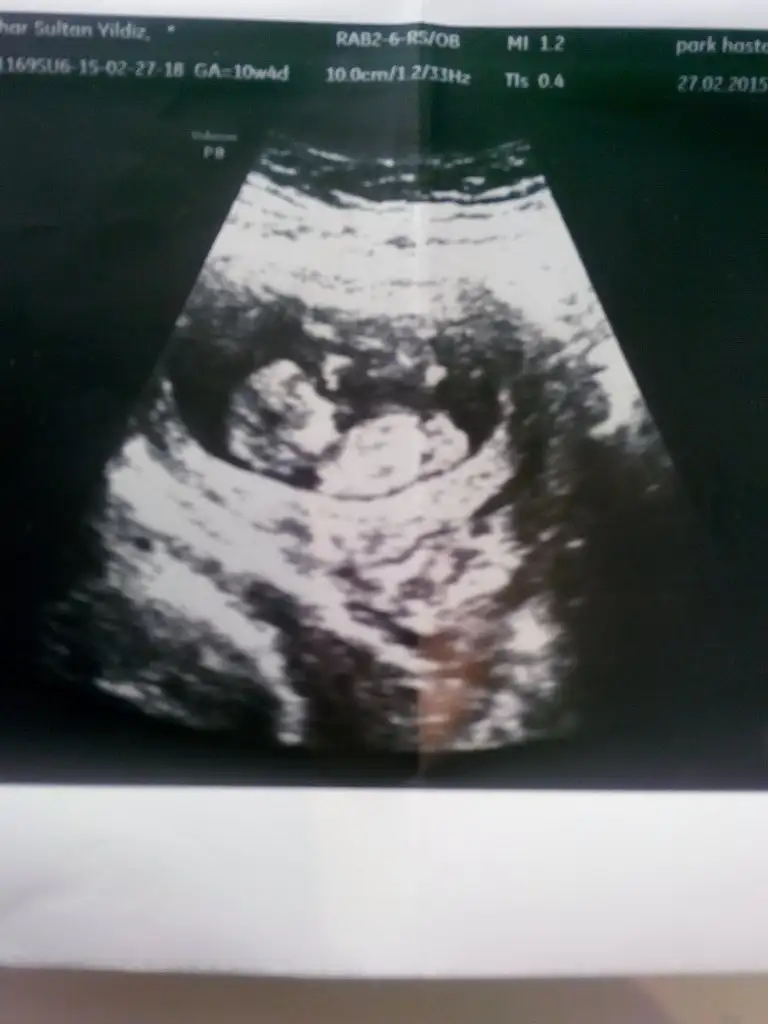

Erkek gibi geldi bana canım. Doktor bir şey dedi mi?Benim bebegime de bakar misiniz 13+4 dedi dr.

Evet canım.. Normalde pek anlamıyorum, herkese söylemiyorum o yüzden, görebildiğime.. ama sanki paralel gibi değil nub. Tabi o kordondur, başka bir şeydir bilmiyorum.. Bana öyle geldi :) Allah gönlüne göre hayırlı sağlıklı bir evlat versin inşallahöğrenirsem mutlaka yazacam caım.. teşekkrü ederim tahminin için. sende nubun ucu havaya kalkık oldugu içinmi erkek dedin kuzum?

1 tane kizim var 2. Kiz geliyor diyorsunCanım ben senin bebeğinin önceki fotoğrafını da hatırlıyorum bana hep kız gibi geliyor.

Canım ben uzman değilim sadece tam net çıkıntı göremiyorum hem de maşAllah ultrason fotoğraflarında yüzü ayrı bir tatlı çıkıyo. Yoksa erkek de olabilir. Doktor hiçbir şey demiyor mu?1 tane kizim var 2. Kiz geliyor diyorsuninsallah canim.asya m gelecek yani.ismi bile hazir.hosgele sefa gele saglikla gele insallah hepsi

Demedi.16. Haftam ama ben bacak arasi gordum sanki bostu cikinti yoktu.ilk baslarda erkek hissediyordum simdi kiz hissediyorum 2 haftadir.hayirlisi bakalimCanım ben uzman değilim sadece tam net çıkıntı göremiyorum hem de maşAllah ultrason fotoğraflarında yüzü ayrı bir tatlı çıkıyo. Yoksa erkek de olabilir. Doktor hiçbir şey demiyor mu?

16 hafta çok güzel bir hafta niye söylemiyorlar anlamıyorum ki. Ama annesi eğer kızsa çok güzel bir bebek herhalde. Allah nazarlardan korusun hep sevimli çıkıyor maşAllah :)Demedi.16. Haftam ama ben bacak arasi gordum sanki bostu cikinti yoktu.ilk baslarda erkek hissediyordum simdi kiz hissediyorum 2 haftadir.hayirlisi bakalim